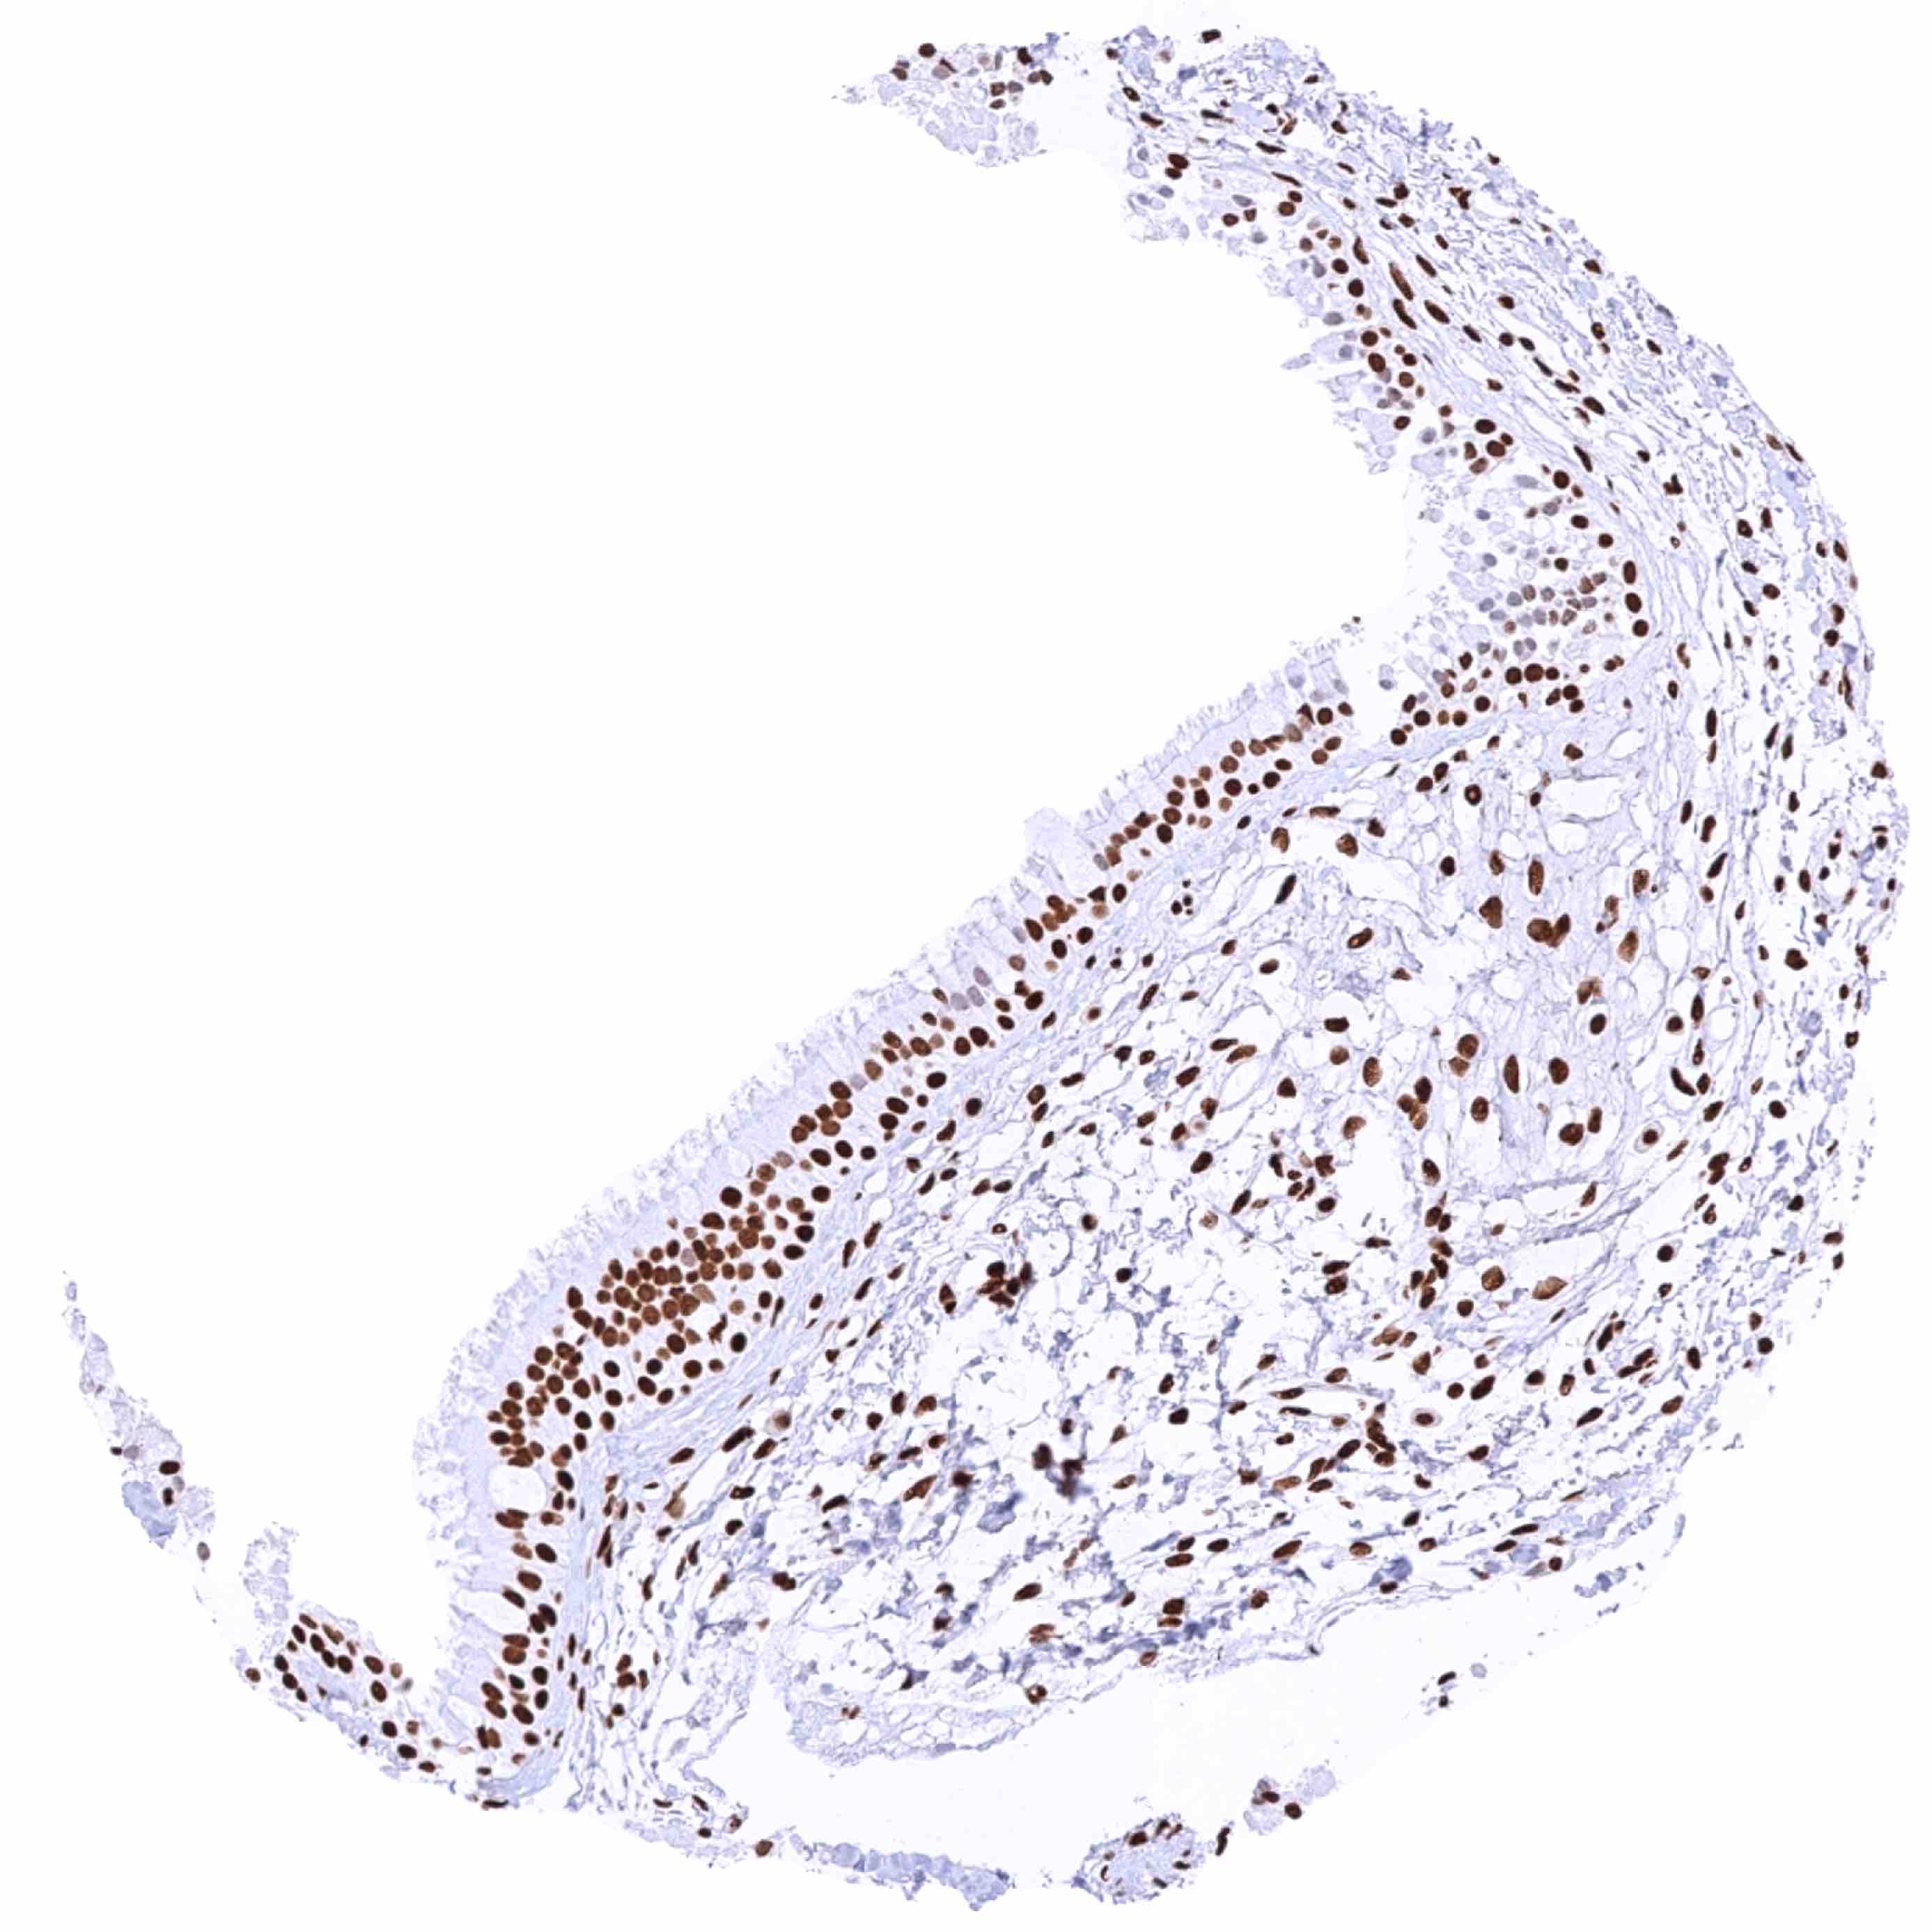

Esophagus, squamous epithelium – HMGB1 staining intensity is strongest in the basal and suprabasal cell layers and countinuously decreases towards the superficial cell layers